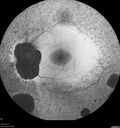

Retinitis Pigmentosa - X-linked Recessive324 views60 year old man The vision in the right eye is blurry recently. He has trouble with night vision for about 3 years. His brother has eye disease in Michigan.

VA OD: Dcc20/32-1 PHNI NccJ1-1

VA OS: Dcc20/20 NccJ1+-1

IOP: TP: OD:36 OS:18

He has pseudoexfoliative glaucoma in the right eye.